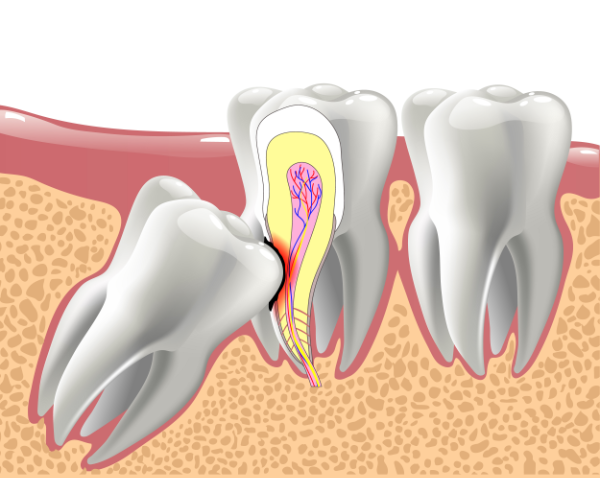

Die Weisheitszähne sind die hintersten Backenzähne auf jeder Seite im Ober- und Unterkiefer. Von der Mitte des Gebisses aus gezählt handelt es sich jeweils um den achten Zahn. Deshalb werden die Weisheitszähne auch „Achter“ genannt. Viele Patienten haben Probleme mit den Weisheitszähnen, weil sie schräg liegen oder zu wenig Platz haben. Nicht selten muss sie der Zahnarzt ziehen oder ein Kieferchirurg in einer OP entfernen.

Die Weisheitszähne sind bei jedem Menschen von Geburt an angelegt. In der Regel brechen sie erst im Erwachsenenalter als letzte Zähne durch – bei den meisten Menschen im Alter zwischen 18 und 25 Jahren. Alle anderen bleibenden Zähne sind bereits im Alter von etwa 15 Jahren sichtbar. Ist im Kiefer zu wenig Platz, bleiben die Achter manchmal teilweise (teilretiniert) oder ganz im Kiefer eingeschlossen (retiniert). Es gibt auch Menschen, die nicht alle vier oder überhaupt keine Weisheitszähne ausbilden.

Sie müssen Ihre Weisheitszähne nur entfernen lassen, wenn es medizinisch notwendig ist. Sind die Zähne gesund und haben ausreichend Platz, können sie erhalten bleiben und ihre Funktion als Backenzähne erfüllen. Sind die Zähne noch unter dem Zahnfleisch verborgen, erkennt Ihr Zahnarzt auf einem Röntgenbild, wie sie sich voraussichtlich entwickeln. Schon ab einem Alter von etwa 15 Jahren ist zu erkennen, ob sie gerade wachsen oder schräg im Kiefer liegen.

- Der Kiefer ist zu klein und die Weisheitszähne liegen schräg.

- Die Weisheitszähne drücken auf Nachbarzähne und schädigen diese.

Tipp: Schieben Sie die OP nicht auf die lange Bank, wenn Ihr Zahnarzt dazu rät, die Weisheitszähne entfernen zu lassen. Je weiter die Zähne ausgebildet sind, desto schwieriger kann es werden, sie zu ziehen. Denn manchmal liegen die Zähne mit ihren bereits ausgebildeten Wurzeln sehr dich an einem Nerv – und das Risiko, die Gesichtsnerven beim Entfernen zu schädigen, steigt.